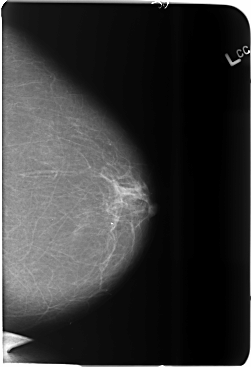

B_3685_1.LEFT_CC

LEFT_CC LINES 5872 PIXELS_PER_LINE 4016 BITS_PER_PIXEL 12 RESOLUTION 50 NON_OVERLAY